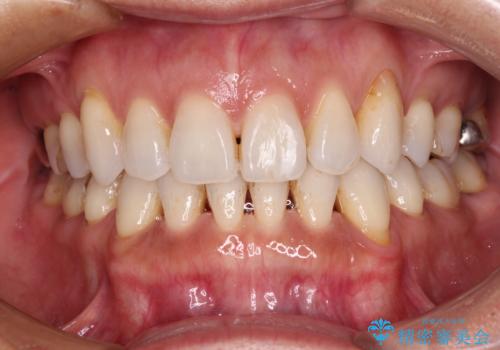

抜歯矯正の後戻りをインビザライン・ライトで解消

- 下顎前歯を中心に、以前行った矯正治療の後戻りが気になるとのことで来院された患者様です。

後戻りは軽度であったため、インビザライン・ライトにて治療を行うこととしました。

矯正治療後は、再度後戻りすることを極力回避するために、下顎前歯の舌側を細いワイヤーを用いて保定することとしました。